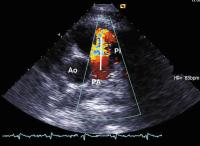

Abbildung 2: Kurze Achse in Höhe der Herzbasis (Farbdoppler): breiter Pulmonalinsuffizienzjet als Ausdruck der höhergradigen Pulmonalinsuffizienz (PI); Ao = Aorta, PA = Pulmonalarterie

Keywords: EchokardiogrammEchokardiographieEndokarditisFarbdopplerHerzKardiologiePulmonalklappe